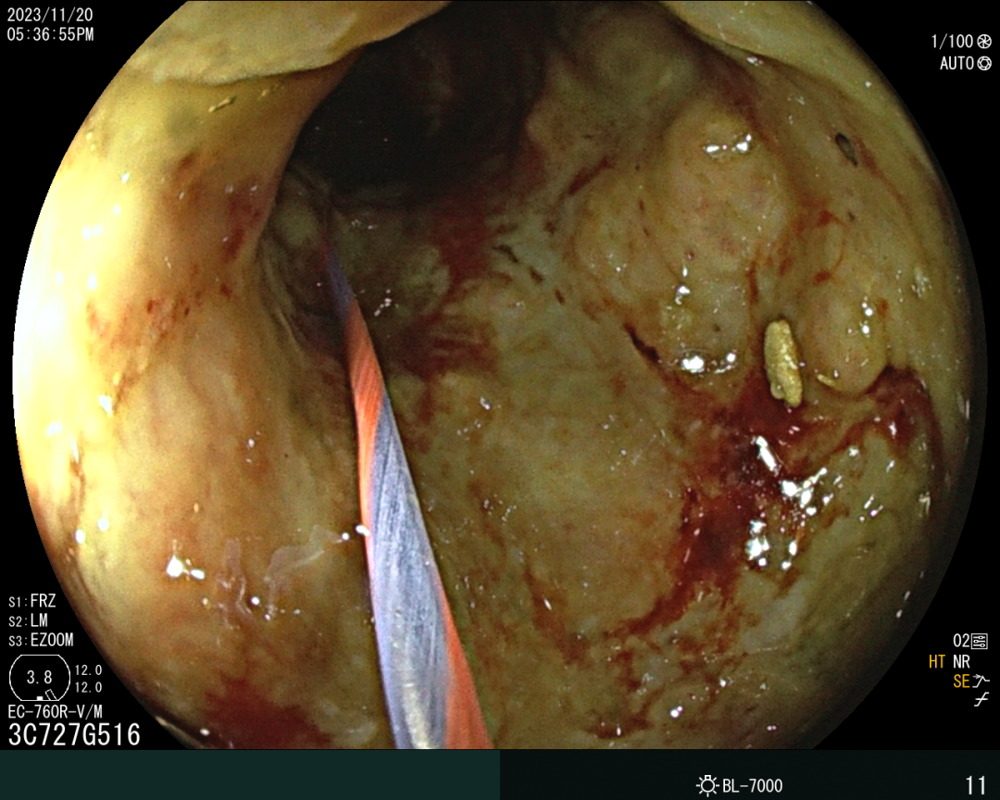

病例(lì)資料:患者,劉某某,男,73歲,因大便未解6天入院,伴有腹部脹痛(tòng),無嘔吐。入院查體;心(xīn)肺無異常、腹彭隆、壓(yā)痛、叩診呈鼓音(yīn),入院後急診腹部(bù)CT提示(shì)。乙狀結腸占位(wèi)並腸道梗阻(zǔ),急診腸鏡示:直乙交界新生物並腸道狹窄。患者於2023年11月(yuè)20日在介入室行腸鏡下腸道支架置入(rù)術,術中腸道流出糞水,術後第一天患者無腹痛(tòng)、腹脹,肛門恢複排便排氣,後複查CT示(shì)腸腔(qiāng)積(jī)氣積(jī)液明顯好轉,臨床療(liáo)效顯著。

(左)支架置入前置入導絲